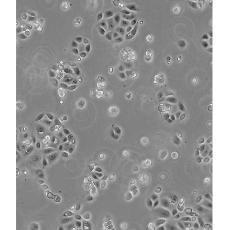

SW 1990

產(chǎn)品名稱 SW 1990

中文名稱 人胰腺癌細(xì)胞

生長特性 adhere

形態(tài)特征 epithelial

細(xì)胞描述 1978年從胰腺外分泌腺的胰腺腺癌II期患者的脾轉(zhuǎn)移灶中建立了SW 1990細(xì)胞株。 報(bào)道該細(xì)胞的植板率為29%。